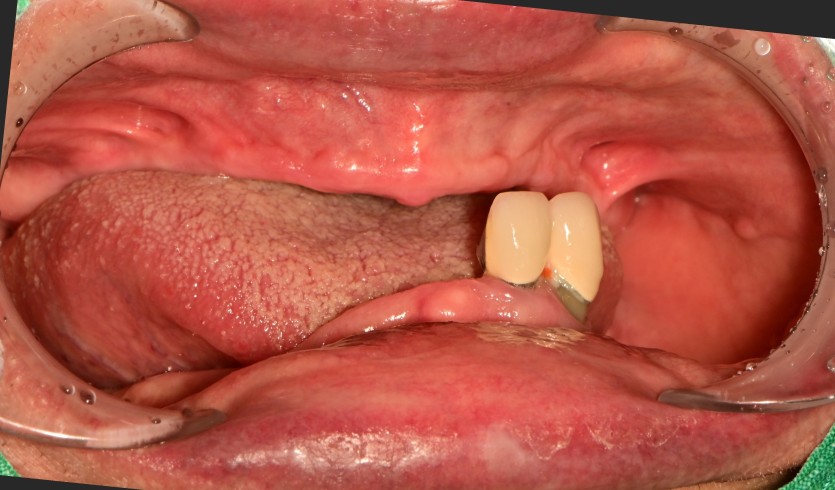

만 65세 상, 하악 전체 임플란트 증례

상,하악 전체 임플란트 증례입니다.

18개의 임플란트로 완성하였습니다.